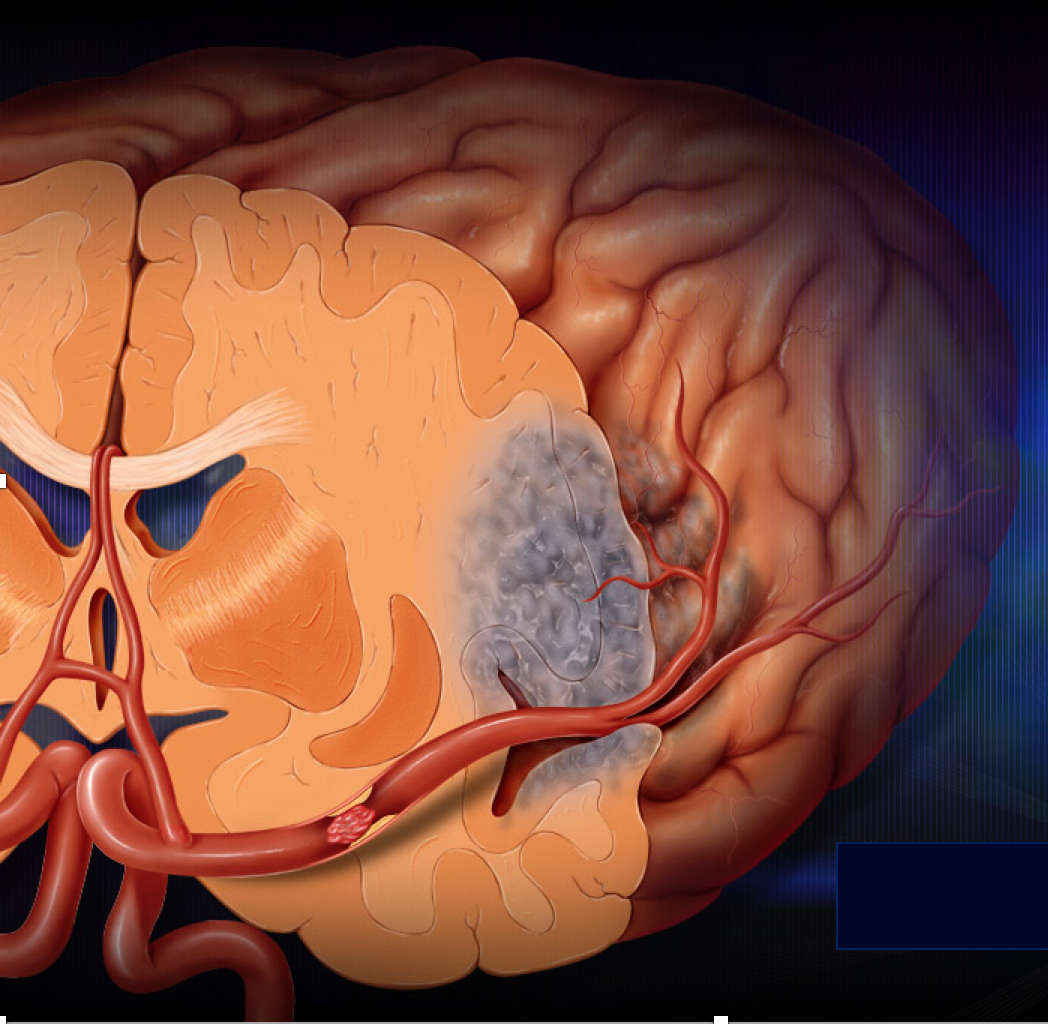

Recently, the world was saddened to learn of the surprising death from stroke of another famous Hollywood celebrity from heart-related issues.

On February 25, 2017, we learned that Mr. Bill Paxton passed away following complications following open heart surgery.

Bill Paxton was famous for acting in a number of Hollywood blockbuster hits including “Twister”, “Aliens” and “Titanic”.

At the present time, limited information is available to the public and press concerning Mr. Paxton’s... Continue reading.